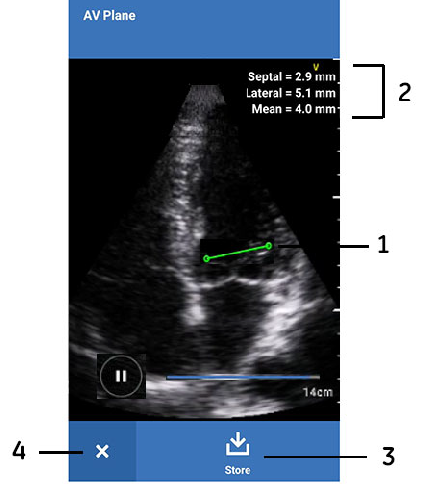

AV Plane measurement

- Mitral annular plane

- Measurement results

- Store button

- Close button

A line representing mitral annular plane is tracked for the whole heart cycle.

- The AV Plane app finds the mitral annular excursion with respect to probe surface.

Septal, lateral and mean of mitral annular excursion values display on the image screen. - Press Store to save the entire video while it is playing.

- Press Pause and press Store to save the still image along with the measurements.